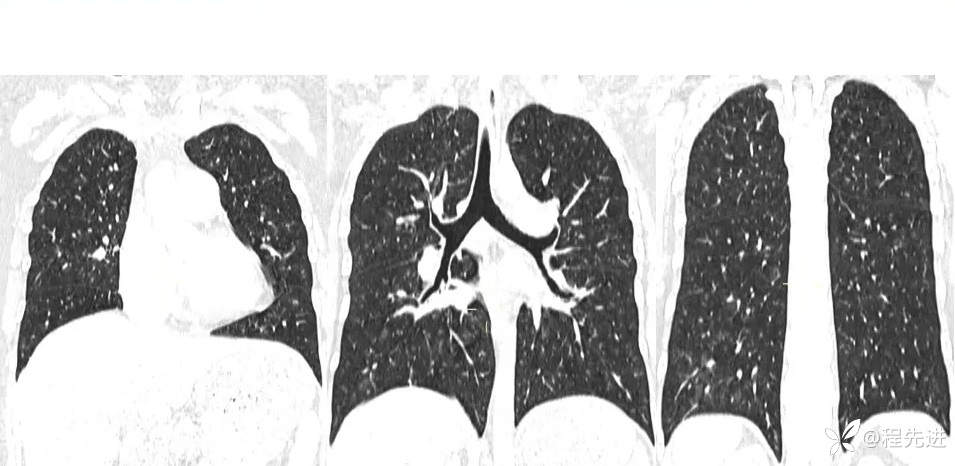

一月余前CT:

患者性别:女

患者年龄:26岁

主诉:咳嗽气促11个月

现病史:患者11个月前无明显诱因下出现咳嗽,无痰,干咳为主,伴有胸闷、气促,活动后加重,无发热,畏寒及胸痛、咯血、晕等,曾在外院治疗,诊断为特发性肺动脉高压。